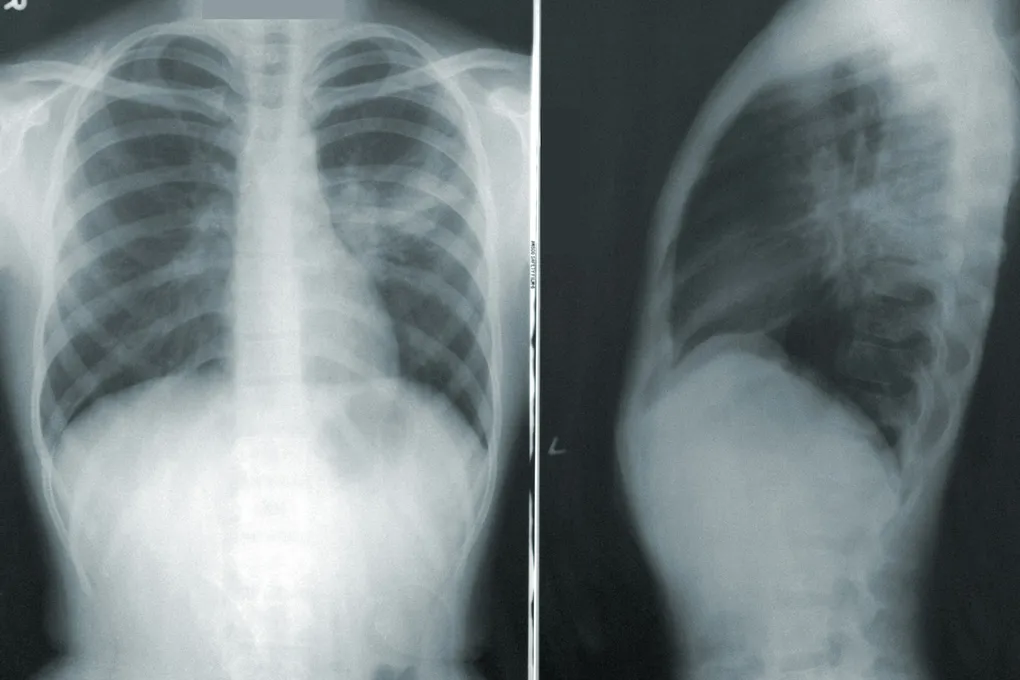

Как это было: добровольцы, маски и нанолисты

Исследователи приготовили два типа сверхчистых нанолистов оксида графена: маленькие и сверхмаленькие. Затем создали аэрозоль, который 14 здоровых участников вдыхали через маску. Сеанс длился два часа, с перерывами, чтобы дыхание у всех было одинаковым. Через несколько недель добровольцы вернулись, чтобы вдохнуть другой тип графена или просто чистый воздух для сравнения. Настоящая научная добровольческая служба!

Результаты? Никаких острых нарушений в работе лёгких, сердца и сосудов. Не появилось и признаков системного воспаления. Однако в лабораторных тестах «в пробирке» учёные заметили умеренное повышение тромбогенности — способности материала запускать свёртывание крови. Это важный сигнал: нужно изучать дальше.